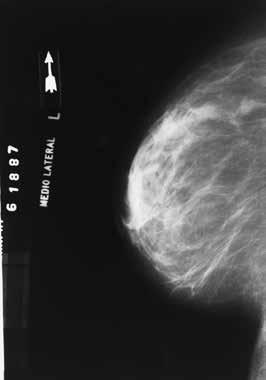

How do I know if I have dense breasts?

Women cannot self-diagnose dense breasts. The National Cancer Institute notes that only a radiologist can determine if a woman has dense breasts, and that’s only possible after a mammogram.

What is the significance of breast density?

Breast density and breast cancer are linked, which underscores how important it can be for women to discuss breast density with their physicians. The National Cancer

Institute notes that dense breasts are not considered an abnormal breast condition or a disease, though they are a risk factor for breast cancer. Women determined to have dense breasts have a higher risk of breast cancer than women with fatty breasts.

The CDC notes that dense tissue can hide cancers, as the fibrous and glandular tissue in breasts, which is more abundant in dense breasts than fatty breasts, looks white on a mammogram. That’s significant, as tumors also look white on mammograms, which means it’s easy to mistake a small tumor for fibrous and glandular tissue.

What can I do if I have dense breasts?

It’s important that women with dense breasts open a dialogue with their physicians. This is especially important when switching physicians, as a new doctor can consider this when treating a patient for the first time. Doctors may recommend certain tests to women with dense breasts, particularly after considering a woman’s age and family history of breast cancer. The CDC notes that additional testing can produce a false positive result, so women can discuss that likelihood as well. But in some cases, a breast ultrasound or a breast MRI may detect a tumor that a mammogram did not find, so additional testing should not be written off.

Breast density and breast cancer are linked, but the NCI notes that research has indicated that women with dense breasts are no more likely to die from breast cancer than women with fatty breasts. More information about breast density can be found at cancer.gov.